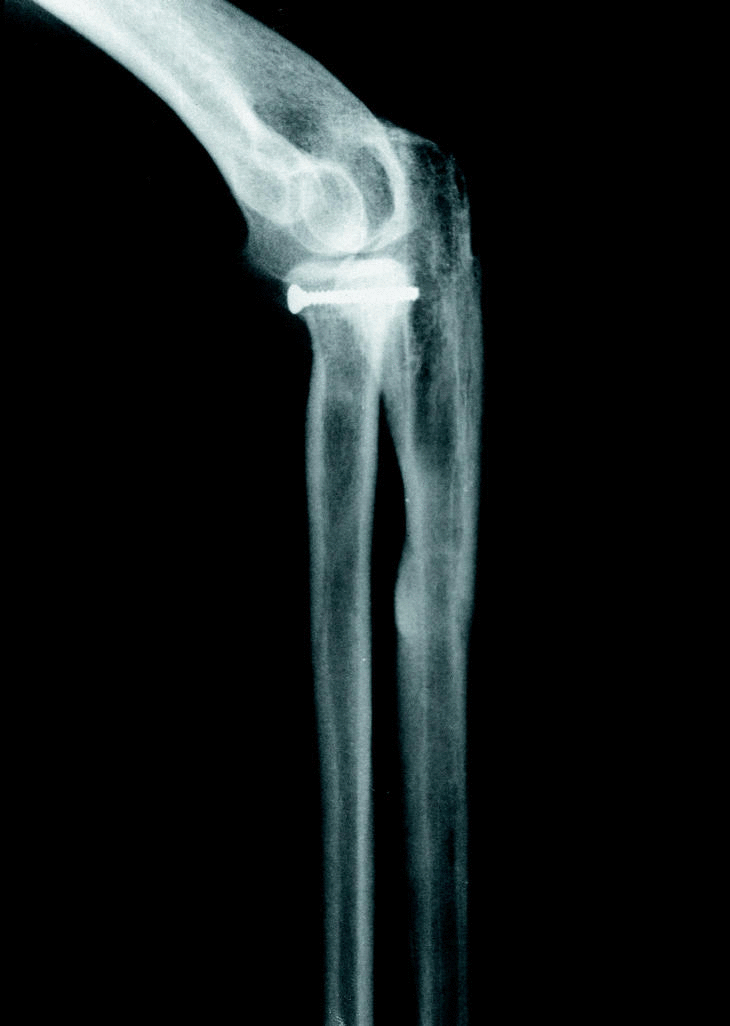

Desde mayo de 1995 hasta febrero de 2000, se utilizó el clavo encerrojado de Lefèvre en 12 casos. Se trataron de 5 osteosíntesis en fracturas de cúbito y radio, 4 fracturas aisladas de cúbito, 2 estabilizaciones de fracturas de Monteggia y una luxación de codo con fractura de Monteggia (Fig. 1).

Figura 1. Fractura-luxación de Monteggia asociada a luxación de codo, imagen preoperatoria (caso 11).

El caso más complejo fue el de una mujer de 42 años, laboralmente activa, que presentó tras una caída casual una luxación de codo asociada a una fractura-luxación de Monteggia. Inicialmente se redujo la luxación y se sintetizó el cúbito; tras el control radiológico se apreció una fractura parcelaria de la cabeza del radio que precisó una osteosíntesis directa con tornillo. Después de lograr la consolidación, a los 3 meses, con una completa recuperación funcional del antebrazo se decidió retirar el clavo con anestesia regional (Figs. 1-6).